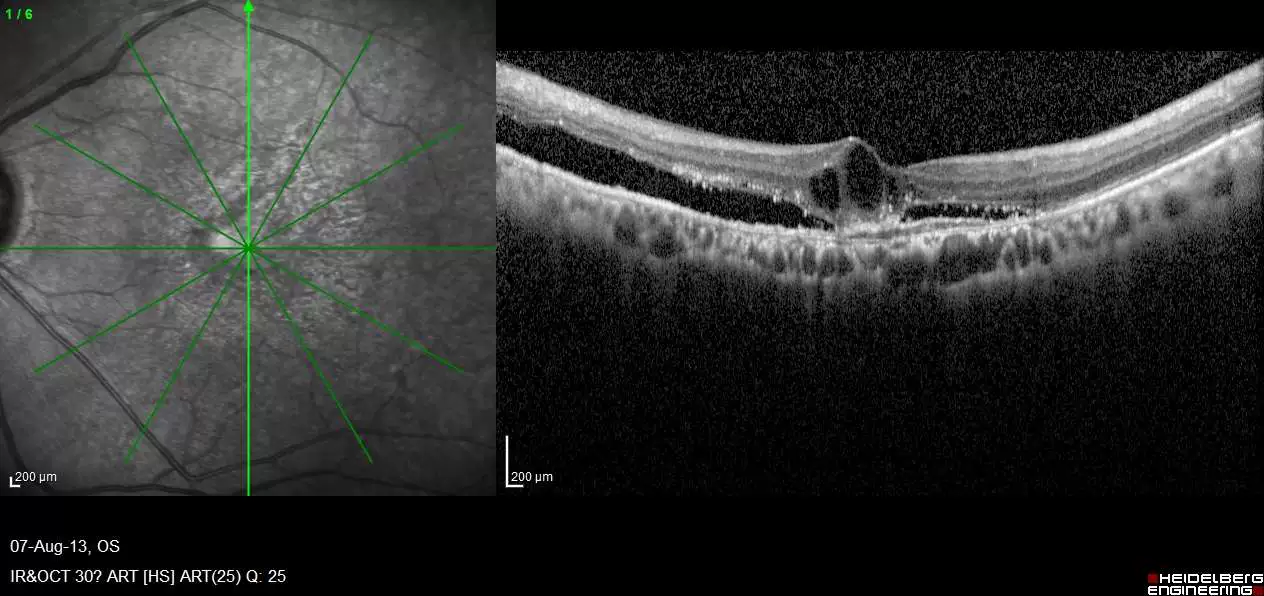

In this synchronous competition, you’ll build a machine learning model to predict treatment response of patients with diabetic macular edema (DME). In order to do so, the competition provides thousands of patients' Optical coherence tomography (OCT) images collected in hospital settings to help predict patients’ response to anti-VEGF treatments 6 months after the loading treatment.